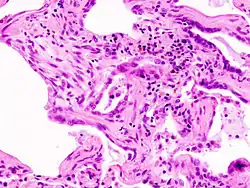

PB: Peribronchiales Bindegewebe, BT: Bronchiolus terminalis, M: zirkuläre Muskelschicht des Bronchiolus, P: Ast der Pulmonalarterie, DA: Ductus alveolares, A: Alveolen, AS: Alveolarsepten.

Färbung mit Hämatoxylin-Eosin (HE).

Das Interstitium (Zwischengewebe) der Lunge befindet sich in Form der so genannten Interalveolarsepten zwischen den Wänden der Lungenbläschen (Alveolen). Letztere stellen, da in ihnen der Gasaustausch zwischen Blut und Luft erfolgt, das eigentliche funktionelle Lungengewebe (Parenchym) dar. Interstitium und Parenchym arbeiten jedoch bei der Lungenmechanik eng zusammen und bilden eine funktionelle Einheit. Das Interstitium ist das Grundgerüst der Lunge und hält die Architektur der Lungenbläschen und damit der Blut-Luft-Schranke während des Atmungszyklus aufrecht. Der Bindegewebsanteil der Interalveolarsepten besteht aus Zellen, vor allem den Bindegewebsbildnern (Fibroblasten), den von ihnen gebildeten Strukturproteinen und Substanzen wie Kollagen, elastische Fasern, Proteoglykane sowie anderen Glycoproteinen.

Den Hauptteil des Interstitiums bilden Kollagenfasern, die bis zu 20 Prozent der Lungentrockenmasse ausmachen. Im Interstitium der Lunge herrscht der Kollagentyp I vor, dem vermutlich die Hauptrolle bei der Aufrechterhaltung der Form und Dehnbarkeit der Lungenbläschen zukommt. Typ IV ist nur in den Basalmembranen der Lungenbläschen und Blutgefäße vorhanden. Kollagen vom Typ III und V ist nur in geringem Umfang (5 bis 10 Prozent) im Lungengewebe ausgebildet.[9] Die elastischen Fasern bilden ein verzweigtes Netzwerk im Interstitium der Lunge. Sie sind die treibende Kraft der Ausatmung (Exspiration).